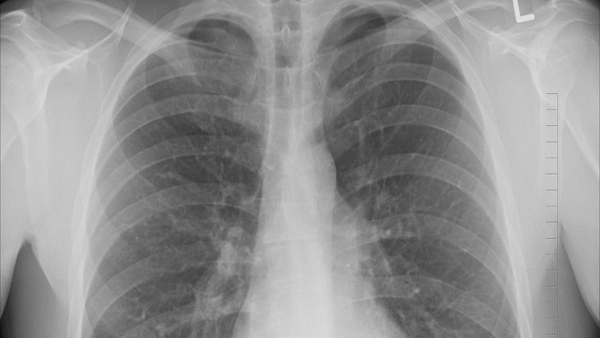

রক্তের পর এবার জীবিত মানুষের ফুসফুসে মিলল প্লাস্টিকের কণা, উদ্বেগ বাড়ছে ক্রমশঃ

রক্তের পর এবার জীবিত মানুষের ফুসফুসে প্ল্যাস্টিকের কণা পাওয়া গিয়েছে। বিশ্লেষণ করা প্রায় সব নমুনায় কণা পাওয়া গেছে বলে প্রকাশিত এক গবেষণার রিপোর্টে এ তথ্য জানানো হয়েছে। গবেষণাটি প্রকাশিত হয়েছে সায়েন্স অফ টোটাল এনভায়রনমেন্ট জার্নালে।

বিজ্ঞানীরা জানিয়েছেন যে প্লাস্টিক কণার দূষণ এখন পুরো পৃথিবীকে গ্রাস করেছে। মানুষ দেহও এখন এই দূষণ থেকে নিরাপদ থাকছে না। এতে 'স্বাস্থ্যের জন্য ঝুঁকির বিষয়ে ক্রমশ উদ্বেগ বাড়াচ্ছে।’ অস্ত্রোপচারে যাওয়া ১৩ জন রোগীর দেহ থেকে বিজ্ঞানীরা নমুনা কোষ সংগ্রহ করেছিলেন। সেই ১৩ জনের থেকে ১১ জনের দেহেই ক্ষুদ্র প্লাস্টিক কণা পেয়েছেন গবেষকরা।

প্রাপ্ত কণাগুলোর মধ্যে সবচেয়ে সাধারণ হচ্ছে, পলিপ্রোপিলিন, যা প্লাস্টিক প্যাকেজিংয়ে ব্যবহৃত হয় এবং লিইথিলিন টেরেফথালেট, যা বোতল তৈরিতে ব্যবহৃত হয়। এর আগের দুটি গবেষণায় ফুসফুসের কোষে একইভাবে উচ্চ হারে প্লাস্টিক কণা পাওয়া গেছে। ইতিমধ্যে প্রাপ্ত তথ্য অনুযায়ী, শ্বাসের মাধ্যম ছাড়াও খাদ্য ও পানীয়ের মাধ্যমে মানুষের দেহে প্লাস্টিকের ক্ষুদ্র কণা প্রবেশ করে বলে জানা গিয়েছিল। উচ্চ মাত্রার প্লাস্টিক কণার সংস্পর্শে থাকা শ্রমিকরা এর ঝুঁকিতে থাকে সবচেয়ে বেশি।

মার্চ মাসে প্রথমবারের মতো মানুষের রক্তে প্লাস্টিক কণা সনাক্ত করা হয়েছিল। পরীক্ষায় দেখা গেছে, কণাগুলো শরীরের ভেতরে ভ্রমণ করতে পারে এবং অঙ্গগুলোতে সংযুক্ত থাকতে পারে। স্বাস্থ্যের উপর এর প্রভাব এখনও অজানা। গবেষণার পরিচালক লরা সাডোফস্কি বলেছেন, 'আমরা ফুসফুসে যে সংখ্যক কণা বা যে আকারের কণা খুঁজে পেয়েছি তা আশা করিনি। এটি বিস্ময়কর, কারণ ফুসফুসের নিচের অংশে শ্বাসনালীগুলো ছোট এবং আমরা আশা করেছিলাম এই আকারের কণাগুলো এতোটা গভীরে যাওয়ার আগে পরিশোধন হয়ে যাবে বা আটকে যাবে।’